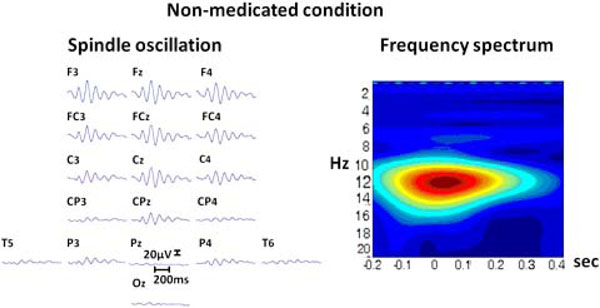

The initiation of propofol resulted in the decrease of spectral variability in the continuous EEG. Fig. (2) displays raw EEG sections with two levels of anesthesia from the non-medicated and medicated conditions. The variability further decreased when reaching to 0.8 µg/mL level, where finally almost all the activity was composed of mono-frequency spectrum 13.20 (±2.56) Hz. These spindle oscillations dominated the EEG recording during the majority of the propofol 1.6 µg/mL levels. These oscillations lasted about 1001.04 (±221.02) milliseconds and had a range of 57.93 (±17.69) µV of amplitude. The spectral plot of a selected EEG segment with a spindle is provided in Fig. (3). As can be observed from the spectrogram, the EEG activity is locked into a narrowband of oscillatory activity of 13 Hz.

Left: The raw EEG segment from 18 electrodes (upper section represents frontal areas). with a spindle oscillation. Right: The spectrogram of the same activity from Cz electrode, vertical axis denotes frequency (Hz); horizontal axis denotes time (seconds).